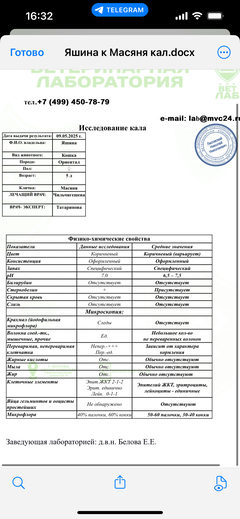

Была куплена в питомнике взрослой. У Масяни начались проблемы с кишечником и она стала подтекать и все пачкать. Надо отдать должное хозяевам - ее обследовали вдоль и поперек - как говорили местные врачи, сдавали много анализов но диагноза так и не поставили.

Ярко выраженная болезненность в области крестца, на обезболе полегче. По результатам приема невролога проведена миелография - множественная компрессия, возможно опухоль, возможно грыжа, нужно удалять...